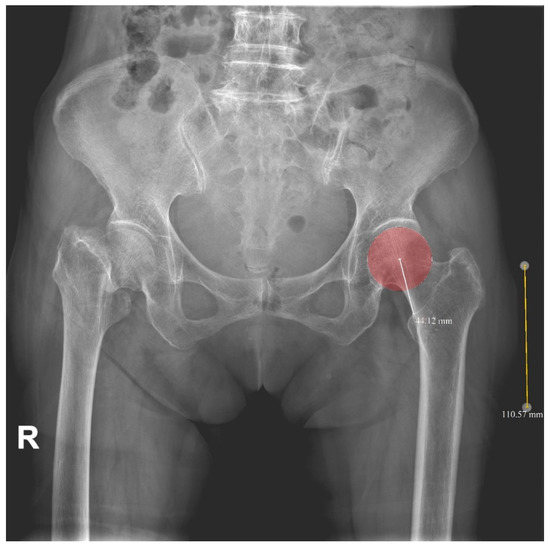

| 2-D HLD | 43.4 ± 4.5 | 43.1 ± 3.9 | 0.710 |